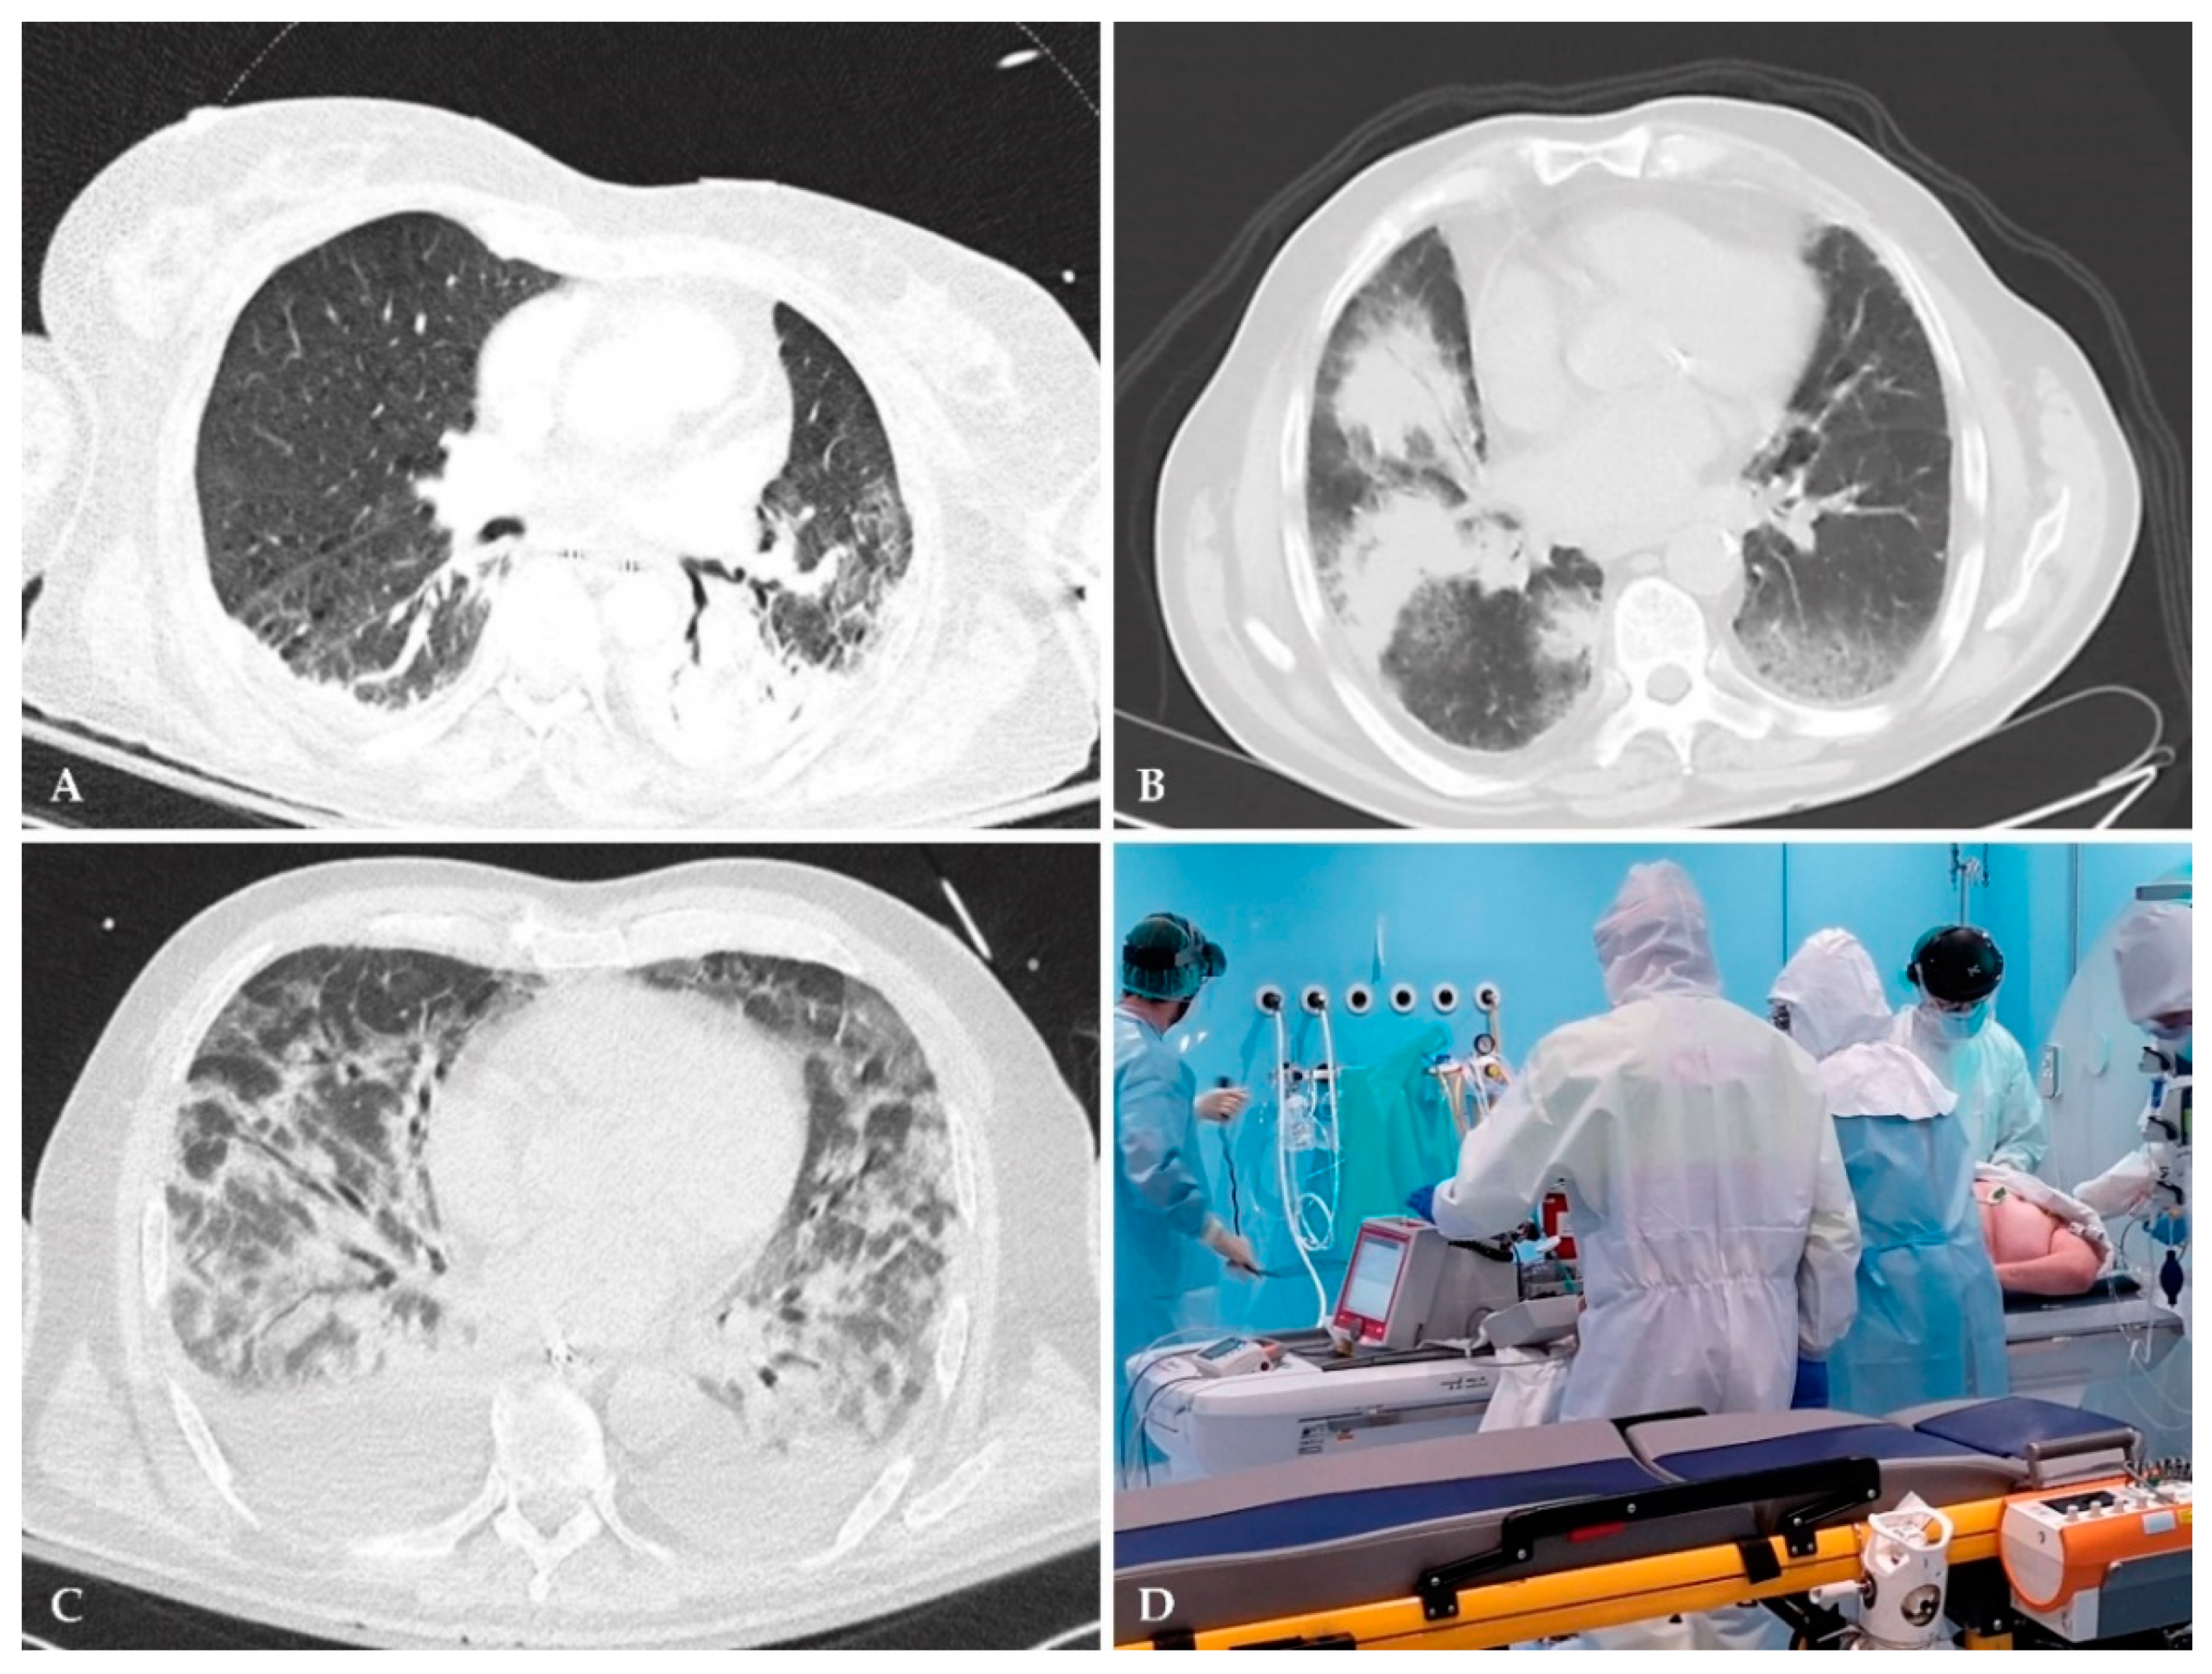

- Mojoli, F.; Bouhemad, B.; Mongodi, S.; Lichtenstein, D. Lung ultrasound for critically ill patients. Am. J. Respir. Crit. Care Med. 2019, 199, 701–714. [Google Scholar] [CrossRef]

- Lichtenstein, D.A.; Mezière, G.A.; Lagoueyte, J.-F.; Biderman, P.; Goldstein, I.; Gepner, A. A-lines and B-lines: Lung ultrasound as a bedside tool for predicting pulmonary artery occlusion pressure in the critically ill. Chest 2009, 136, 1014–1020. [Google Scholar] [CrossRef]

- Dietrich, C.F.; Mathis, G.; Blaivas, M.; Volpicelli, G.; Seibel, A.; Wastl, D.; Atkinson, N.S.; Cui, X.-W.; Fan, M.; Yi, D. Lung B-line artefacts and their use. J. Thorac. Dis. 2016, 8, 1356. [Google Scholar] [CrossRef] [PubMed]

- Lichtenstein, D.; Mezière, G.; Seitz, J. The dynamic air bronchogram: A lung ultrasound sign of alveolar consolidation ruling out atelectasis. Chest 2009, 135, 1421–1425. [Google Scholar] [CrossRef]

- Staub, L.J.; Biscaro, R.R.M.; Maurici, R. Emergence of Alveolar Consolidations in Serial Lung Ultrasound and Diagnosis of Ventilator-Associated Pneumonia. J. Intensiv. Care Med. 2019, 36, 088506661989427. [Google Scholar] [CrossRef]

- Bouhemad, B.; Dransart-Rayé, O.; Mojoli, F.; Mongodi, S. Lung ultrasound for diagnosis and monitoring of ventilator-associated pneumonia. Ann. Transl. Med. 2018, 6, 418. [Google Scholar] [CrossRef]